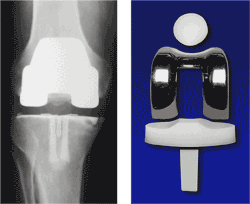

Total Knee Joint Replacement Operation

In a knee replacement operation, the surgeon removes the worn ends of the bones and any remaining hard cartilage and replaces them with metal and plastic parts. The end of the thigh bone (femur) is replaced by a single curved piece of hard metal. The top end of the shin bone (tibia) is replaced by a flat plate of metal fixed into the bone. A plastic bearing is fitted to this plate to act like hard cartilage. The surgeon usually has to adjust the ligaments of the knee to make way for the new joint and to correct any deformity. The interlocking parts of the new metal and plastic parts allow the knee to bend while also making it more stable.